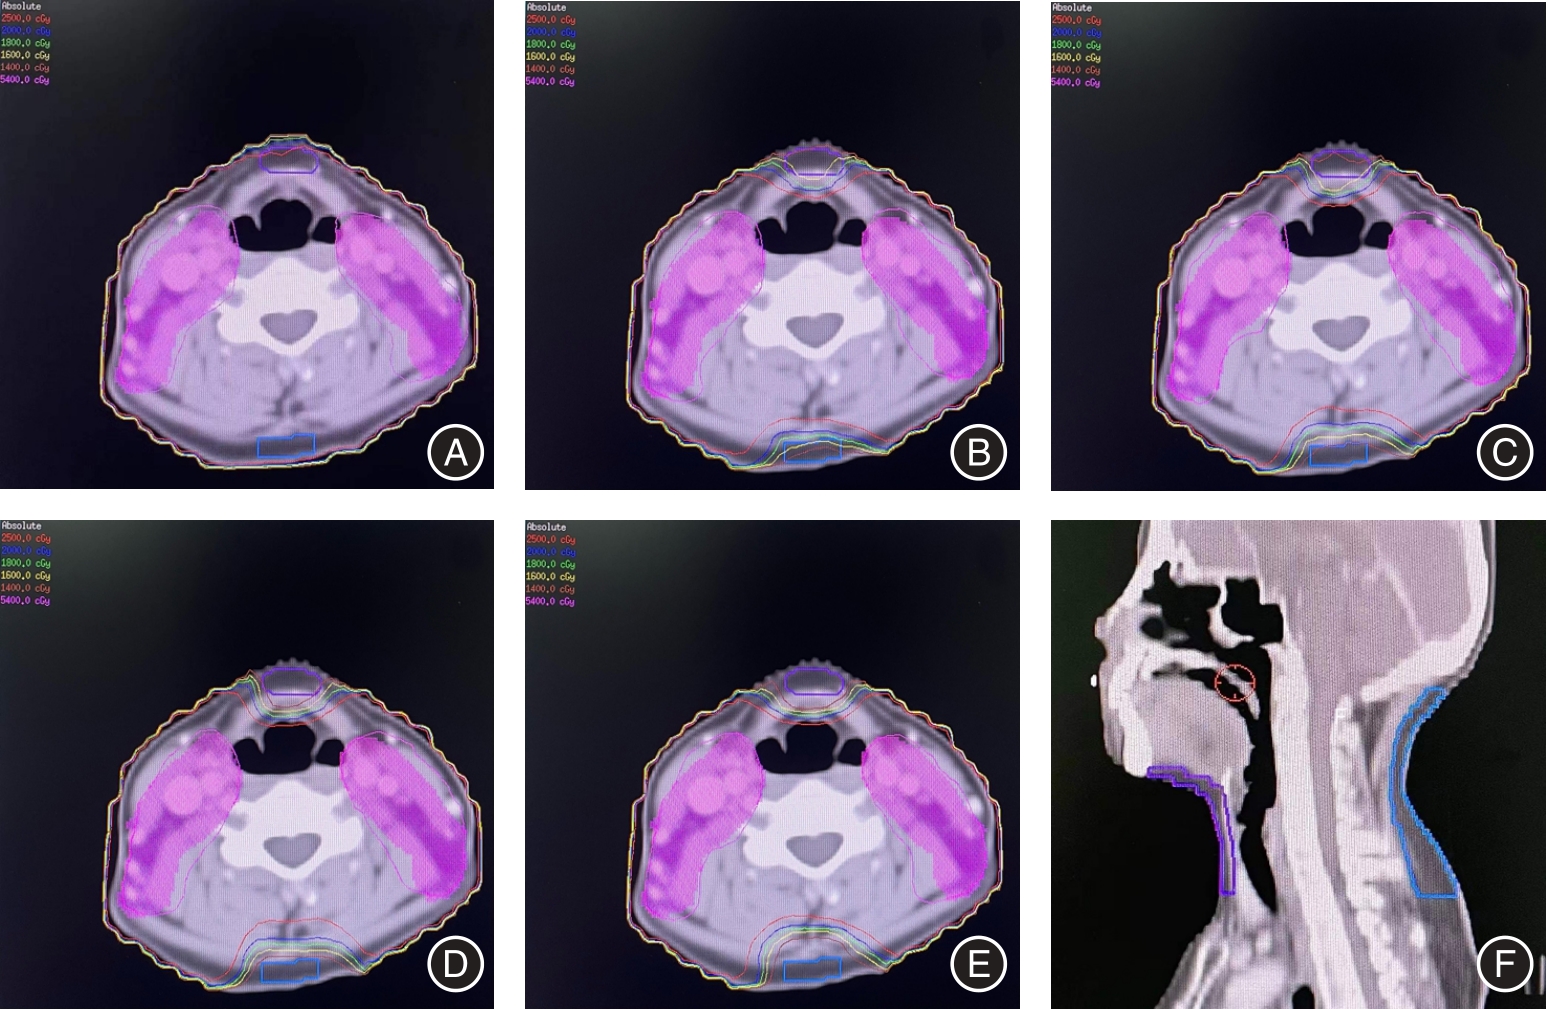

Fei CHEN,Xiaoqin GONG,Yunpeng YU,Tao YOU,Xu WANG,Chunhua DAI,Jing HU.

Feasibility of automatic segmentation of CTV and OARs in postoperative radiotherapy for cervical cancer using AccuLearning

[J]. The Journal of Practical Medicine, 2024, 40(2): 153-157.

Che CHEN,Dehong LUO,Huangfei YU,Qin ZHANG,Xiaochi HU,Shenghua YU,Yajun. LI.

Clinical Application of automatic delineation in whole breast radiotherapy with simultaneous integrated boost to the medial tumor beds

[J]. The Journal of Practical Medicine, 2024, 40(17): 2406-2411.